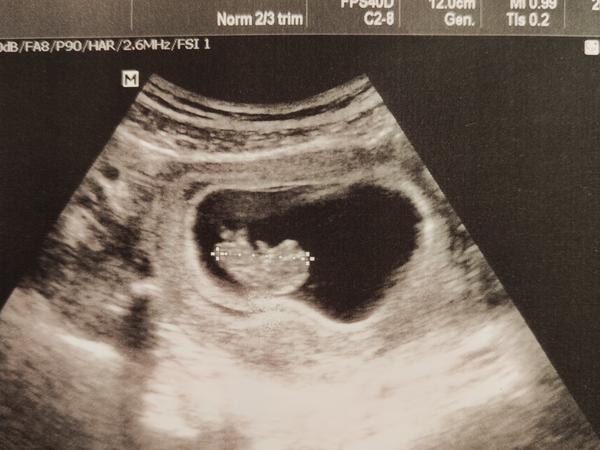

Foto z ultrazvuku

Je pod plodovým vakom druhý vak? Alebo to je niečo iné? Krvná zrazenina? Lekárka sa nevyjadrila. 9tt

@stellarstar myslím to čierne tam hore v ľavo. Pridávam foto kde je niečo podobné a sú to dvojičky.

@jaja8_9 žijem v zahraničí. Ultrazvuk robila len PA a to len priložila, zmerala plod a urobila fotky. Neprehliadla maternicu. Od známej, ktorá pracuje ako sestrička u gynekológa na SK mám info, že to čierne je tekutina, ale nevie sa lepšie vyjadriť z týchto fotiek. Takže niečo tam je určite.

Podľa mňa 1 plod, nič iné. Ale zrejme nie si s takouto odpoveďou spokojná. Jediné čo Ťa ukludni , alebo zbaví z pochybností je návšteva iného lekára...

Dám ti radu už s tým prestaň, nemáš tam ani hematom ani druhý plod. Užívaj TT a bud rada že je všetko ôk a nehľadaj problém tam kde nie je 🙏

Nič tam nie je je tam plod a placenta